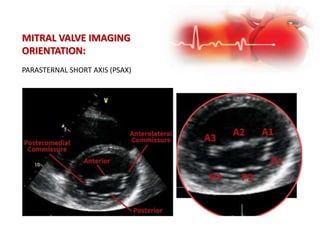

MITRAL VALVE IMAGING

ORIENTATION:

4 standard views to visualize the mitral valve:

1. Parasternal long axis (PLAX)

2. Parasternal short axis (PSAX)

3. Apical 4 Chamber (AP4)

4. Apical 2 Chamber (AP2)

PARASTERNAL SHORT AXIS (PSAX)